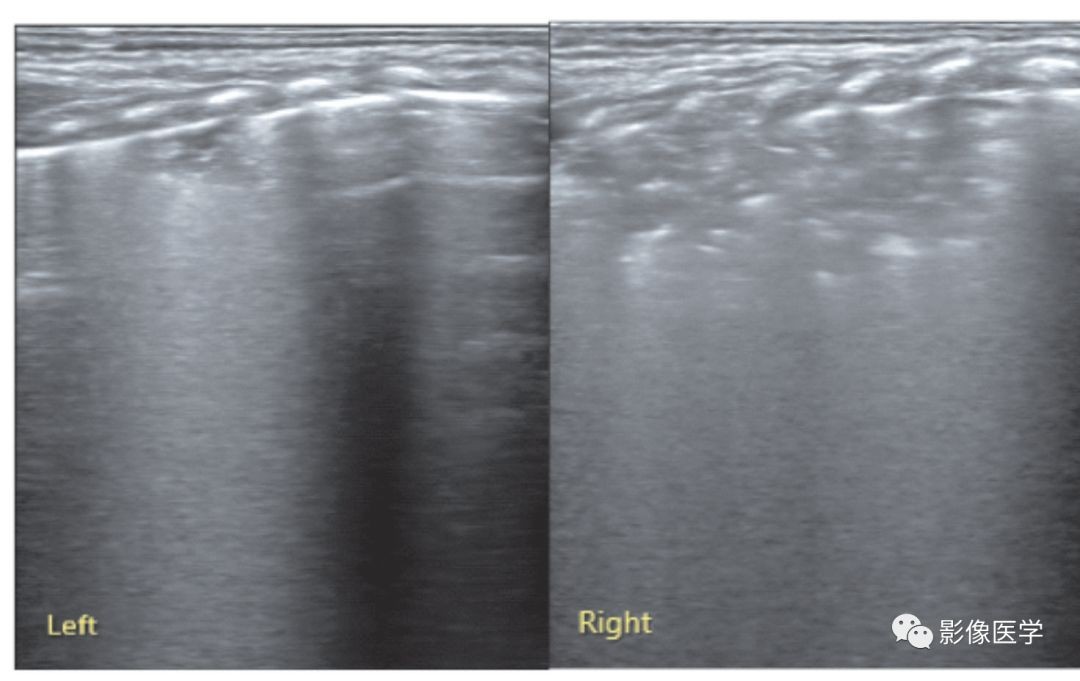

图6-27 轻度肺炎的超声表现:胸膜下实变伴左侧胸腔积液

胎龄37周,宫内窘迫伴出生时窒息,出生后轻度呼吸困难。肺脏超声显示左肺弥漫性胸膜下局灶性实变,胸膜线模糊或消失,并可见明显胸腔积液。由此可见,轻度肺炎可仅有局灶性的小范围实变。